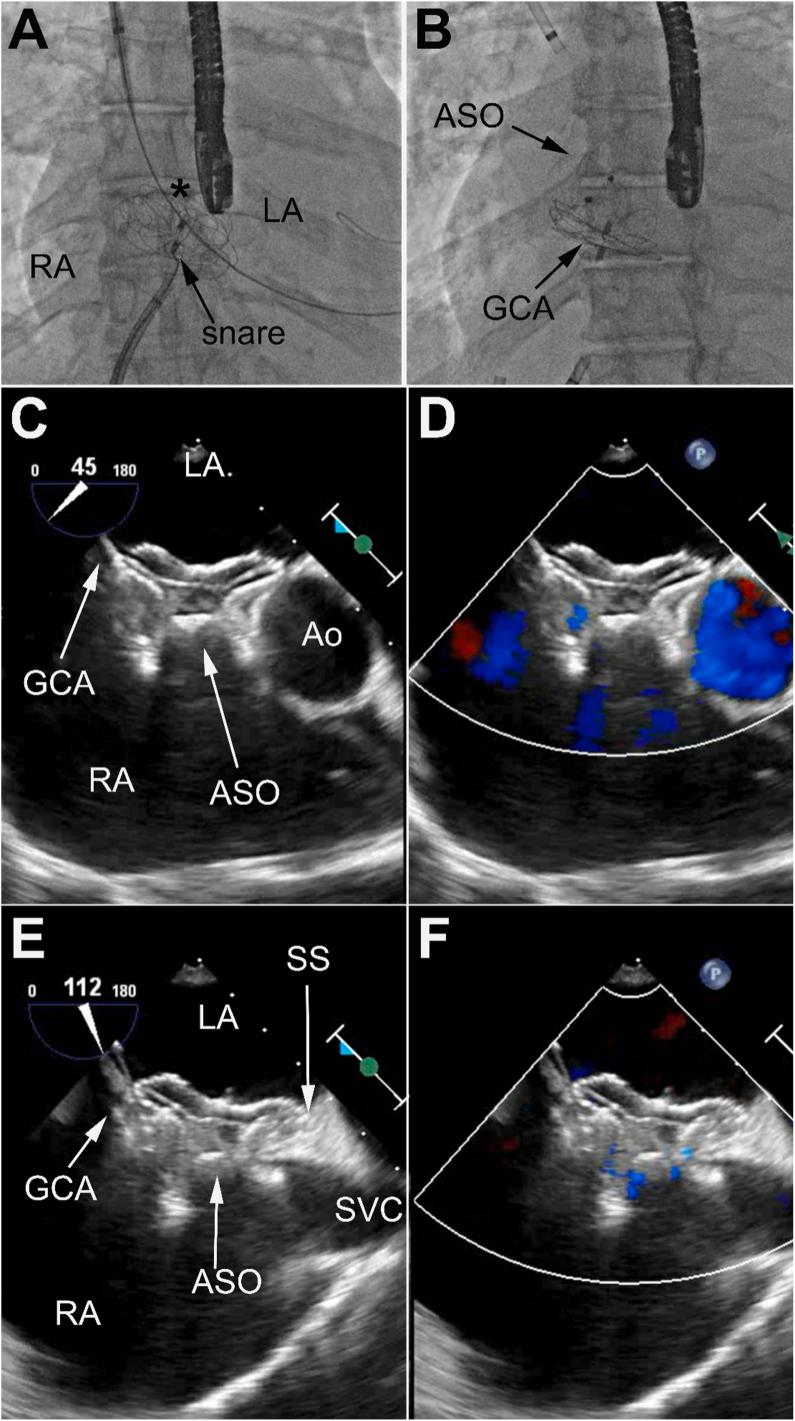

Percutaneous closure of ASD is nowadays preferred and more widely performed over surgical closure. The GORE® CARDIOFORM ASD occluder (GCA) is the latest generation of occluder with promising results as it performed well with high successful implant rates (96%) and showed high efficacy in challenging clinical and anatomical situations. We present the case of a 65 female with a 2.5 cm ASD, left atrial hypertension, deficient retroaortic rim, mobile septum primum and hypertrophied septum secundum. She underwent uncomplicated closure with a 44-mm GCA. However, the patient presented to the emergency room five weeks post procedure and was found to be in atrial fibrillation with rapid ventricular response at a rate of 158 bpm. Further workup showed a dislodged GCA device despite appropriate device placement and size selection based on the published instructions for use. We elected to not remove the 44-mm GCA given that it had become adherent to the septum primum but instead used the stiffer Amplatzer septal occluder to stabilize the GCA and occlude the residual defect. Finally, we highly recommend taking device destabilizing factors into consideration when selecting device size.

如今,经皮封堵房间隔缺损(ASD)比外科手术封堵更受青睐且应用更为广泛。戈尔公司的CARDIOFORM ASD封堵器(GCA)是新一代封堵器,取得了令人瞩目的成果,其植入成功率高(96%),在具有挑战性的临床和解剖情况下也显示出高效性。我们报告了一例65岁女性患者,患有2.5厘米的房间隔缺损、左心房高压、主动脉后缘不足、原发隔活动及继发隔肥厚。她使用44毫米的GCA进行了顺利封堵。然而,患者在术后五周因快速心室反应性房颤(心率158次/分钟)就诊于急诊室。进一步检查发现,尽管根据已发布的使用说明进行了合适的装置放置和尺寸选择,但GCA装置仍发生了移位。鉴于44毫米的GCA已与原发隔粘连,我们选择不取出它,而是使用更硬的Amplatzer房间隔封堵器来稳定GCA并封堵残余缺损。最后,我们强烈建议在选择装置尺寸时考虑装置不稳定因素。